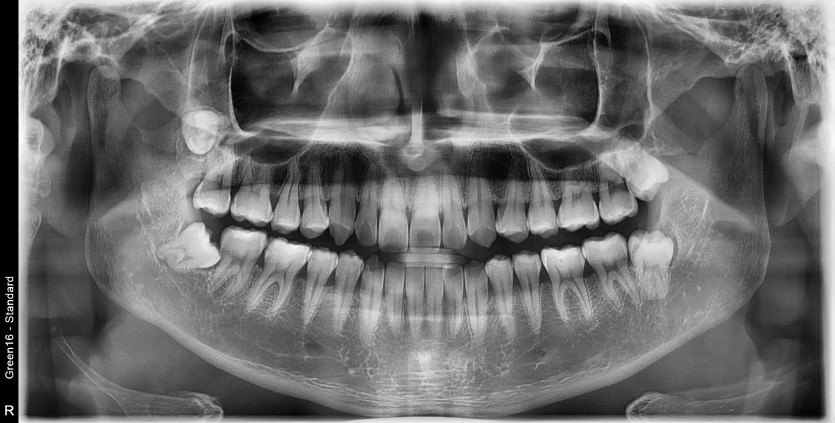

#28,38,48 사랑니 발치

구강 외과 전문의가 당일 발치했습니다.